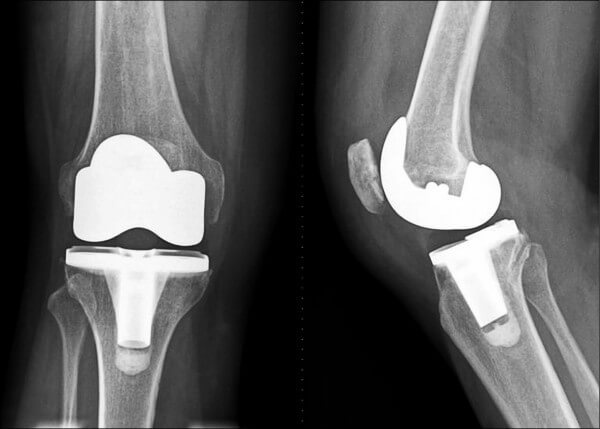

前十字韧带(ACL)撕裂几乎是篮球运动员最怕听到的词。它往往发生在落地不稳或急停转向时,一旦撕裂,至少需要6-9个月才能重返赛场。